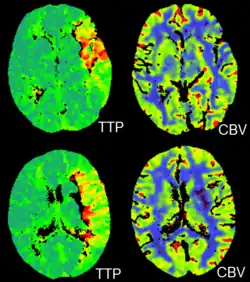

Perfusion Imaging

CT perfusion imaging is a specific form of CT to assess flow through blood vessels whilst injecting a contrast agent.[78] Blood flow, blood transit time, and organ blood volume, can all be calculated with reasonable sensitivity and specificity.[78] This type of CT may be used on the heart, although sensitivity and specificity for detecting abnormalities are still lower than for other forms of CT.[79] This may also be used on the brain, where CT perfusion imaging can often detect poor brain perfusion well before it is detected using a conventional spiral CT scan.[78][80] This is better for stroke diagnosis than other CT types.[80]